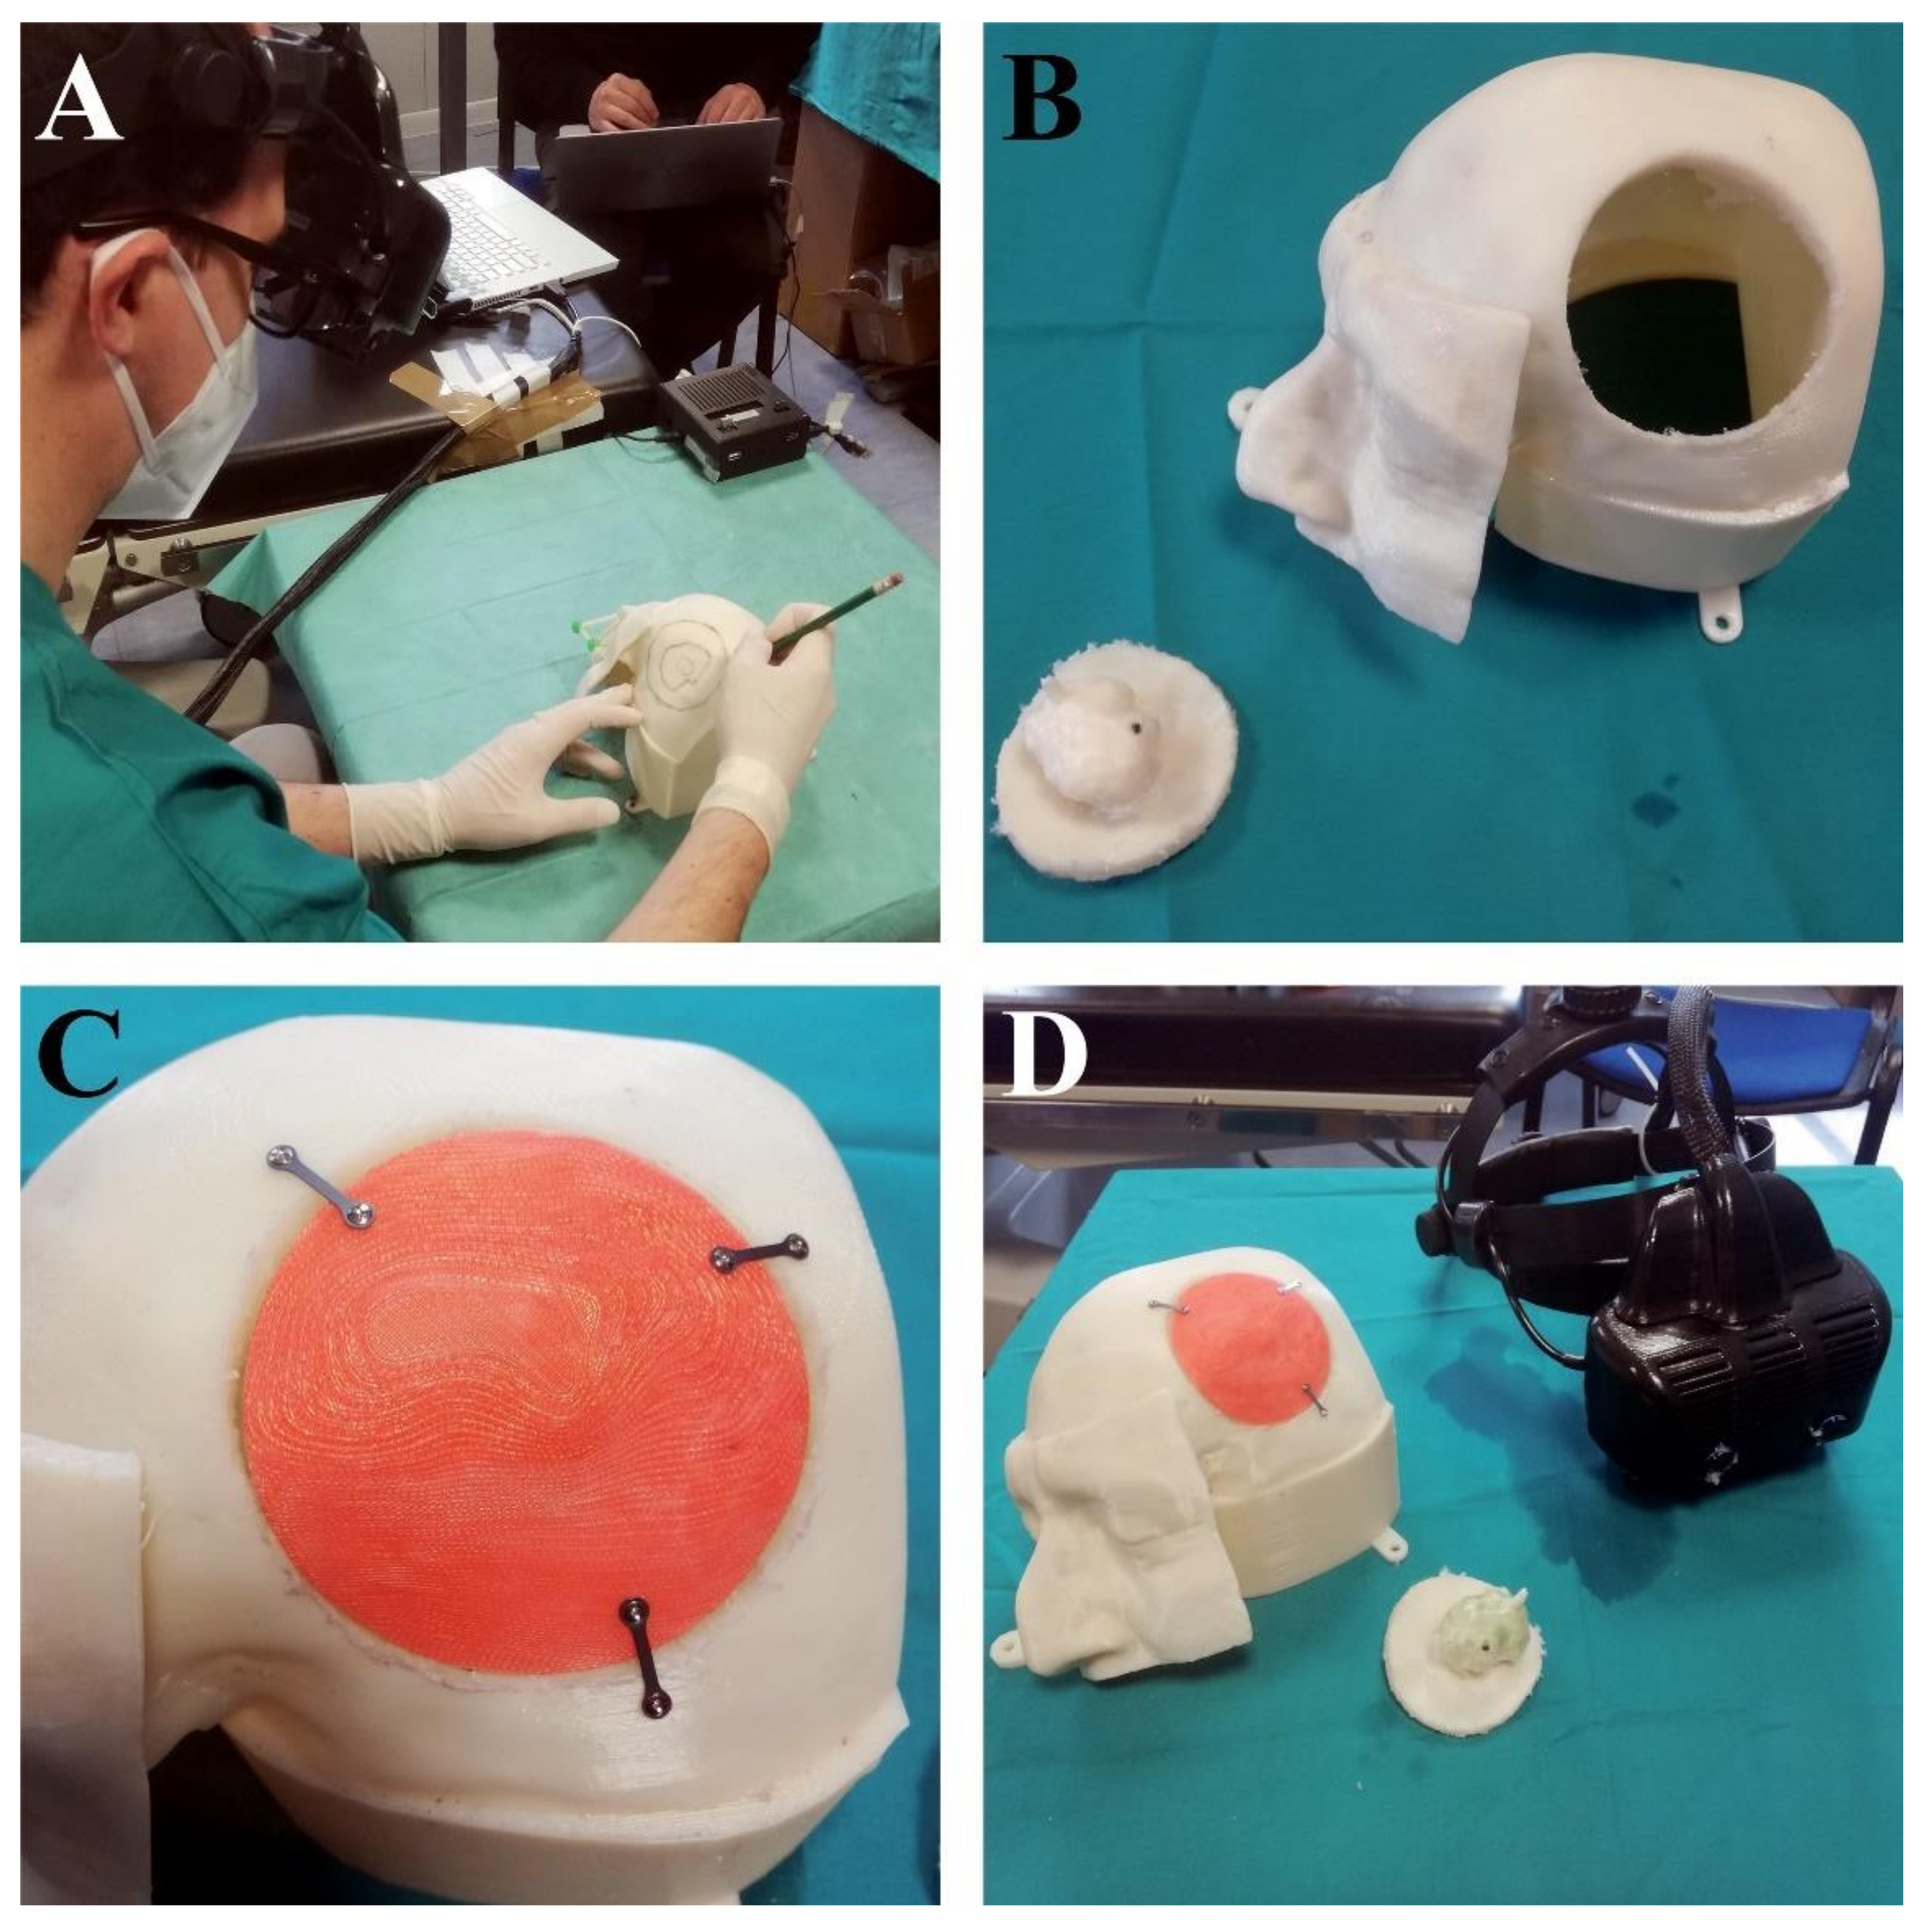

2.2. VOSTARS HMD-Based Surgical Navigation Platform and Template-Based Registration

2.3. AR Visualization Modalities

3. Results